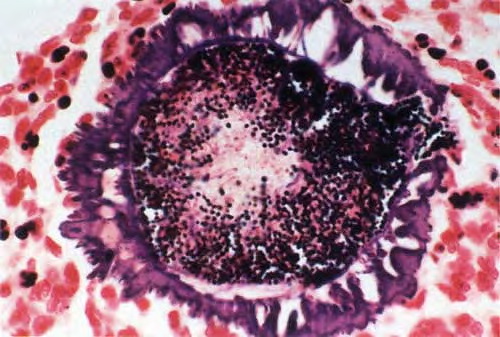

Read MoreBotryomycosis =الداء العنقودي OLYMPUS DIGITAL CAMERA OLYMPUS DIGITAL CAMERA